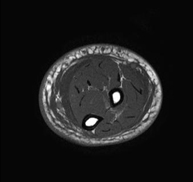

Exploración para el estudio de lesiones en la articulación, como roturas meniscales y de ligamentos cruzados (unicamente detectables mediante esta prueba), condropatía o desgaste del cartílago y multitud de otras alteraciones derivadas de la actividad deportiva y los cambios degenerativos (osteoartrosis). Tiene una duración aproximada de 18 minutos. No emplea radiación ionizante. - RM Pierna